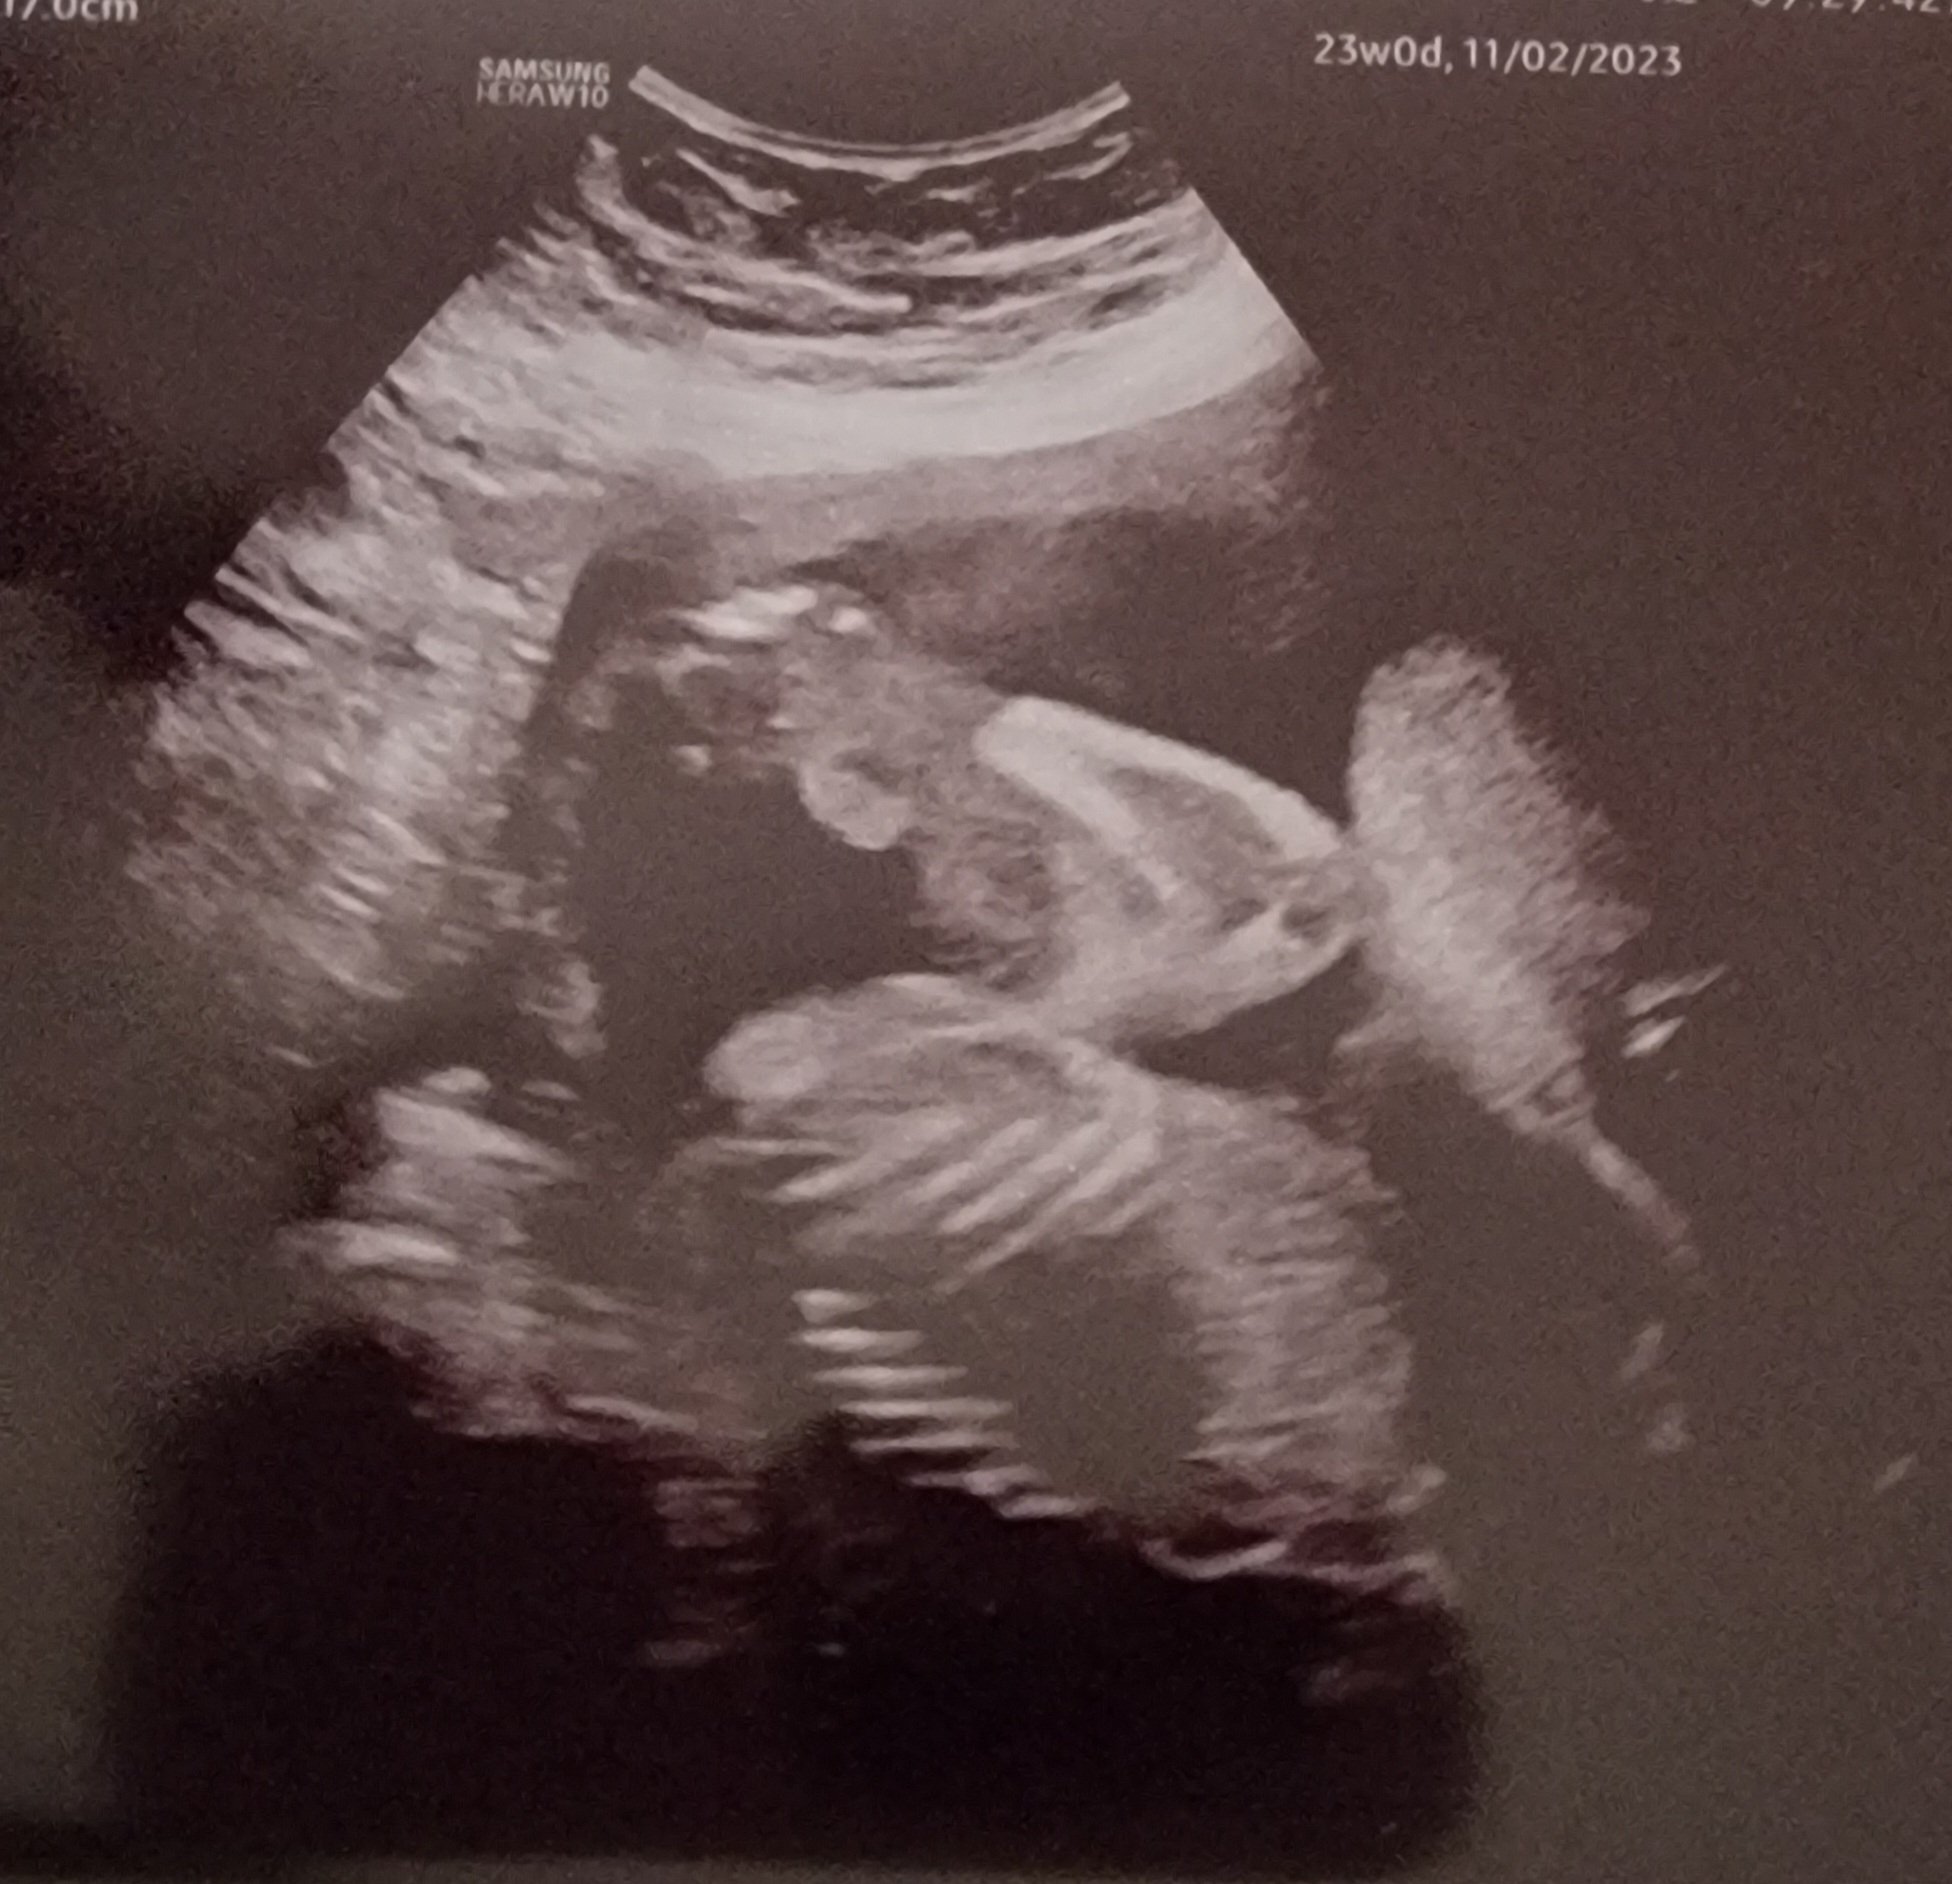

Had my anatomy scan done on Monday! They couldn’t get a good shot of baby’s face. Baby was moving around like crazy. I’ve done 5 anatomy scans before (both of my kids required me to go back for more imaging) - and I’ve never seen a baby move like this. It was wild to see! The tech was really sweet and wrote notes on the images for my kids and DH who couldn’t attend.

Third kid: Due 11/6 Second kid: Dec 2021 First kid: Sept 2019

My sweet baby did not sit still AT ALL the entire scan. I felt so bad as the ultrasound tech was training someone and the trainee had such a hard time with my baby 😂 but anyway, here’s my sweet and very active baby boy!!!!